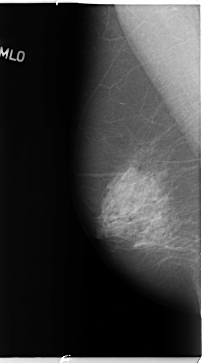

B_3093_1.LEFT_MLO

LEFT_MLO LINES 4648 PIXELS_PER_LINE 2744 BITS_PER_PIXEL 12 RESOLUTION 50 OVERLAY

FILE: B_3093_1.LEFT_MLO.OVERLAY

TOTAL_ABNORMALITIES 1

ABNORMALITY 1

LESION_TYPE MASS SHAPE ARCHITECTURAL_DISTORTION MARGINS ILL_DEFINED-SPICULATED

ASSESSMENT 4

SUBTLETY 3

PATHOLOGY BENIGN

TOTAL_OUTLINES 1